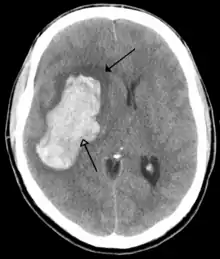

CT scan of a cerebral hemorrhage, showing an intraparenchymal bleed (bottom arrow) with surrounding edema (top arrow)

A stroke is a decrease in blood supply to an area of the brain causing cell death and brain injury. This can lead to a wide range of symptoms, including the "FAST" symptoms of facial droop, arm weakness, and speech difficulties (including with speaking and finding words or forming sentences).[190] Symptoms relate to the function of the affected area of the brain and can point to the likely site and cause of the stroke. Difficulties with movement, speech, or sight usually relate to the cerebrum, whereas imbalance, double vision, vertigo and symptoms affecting more than one side of the body usually relate to the brainstem or cerebellum.[191]

Most strokes result from loss of blood supply, typically because of an embolus, rupture of a fatty plaque causing thrombus, or narrowing of small arteries. Strokes can also result from bleeding within the brain.[192] Transient ischaemic attacks (TIAs) are strokes in which symptoms resolve within 24 hours.[192] Investigation into the stroke will involve a medical examination (including a neurological examination) and the taking of a medical history, focusing on the duration of the symptoms and risk factors (including high blood pressure, atrial fibrillation, and smoking).[193] Further investigation is needed in younger patients.[194] An ECG and biotelemetry may be conducted to identify atrial fibrillation; an ultrasound can investigate narrowing of the carotid arteries; an echocardiogram can be used to look for clots within the heart, diseases of the heart valves or the presence of a patent foramen ovale.[194] Blood tests are routinely done as part of the workup including diabetes tests and a lipid profile.[194]

Some treatments for stroke are time-critical. These include clot dissolution or surgical removal of a clot for ischaemic strokes, and decompression for haemorrhagic strokes.[195][196] As stroke is time critical,[197] hospitals and even pre-hospital care of stroke involves expedited investigations – usually a CT scan to investigate for a haemorrhagic stroke and a CT or MR angiogram to evaluate arteries that supply the brain.[194] MRI scans, not as widely available, may be able to demonstrate the affected area of the brain more accurately, particularly with ischaemic stroke.[194]